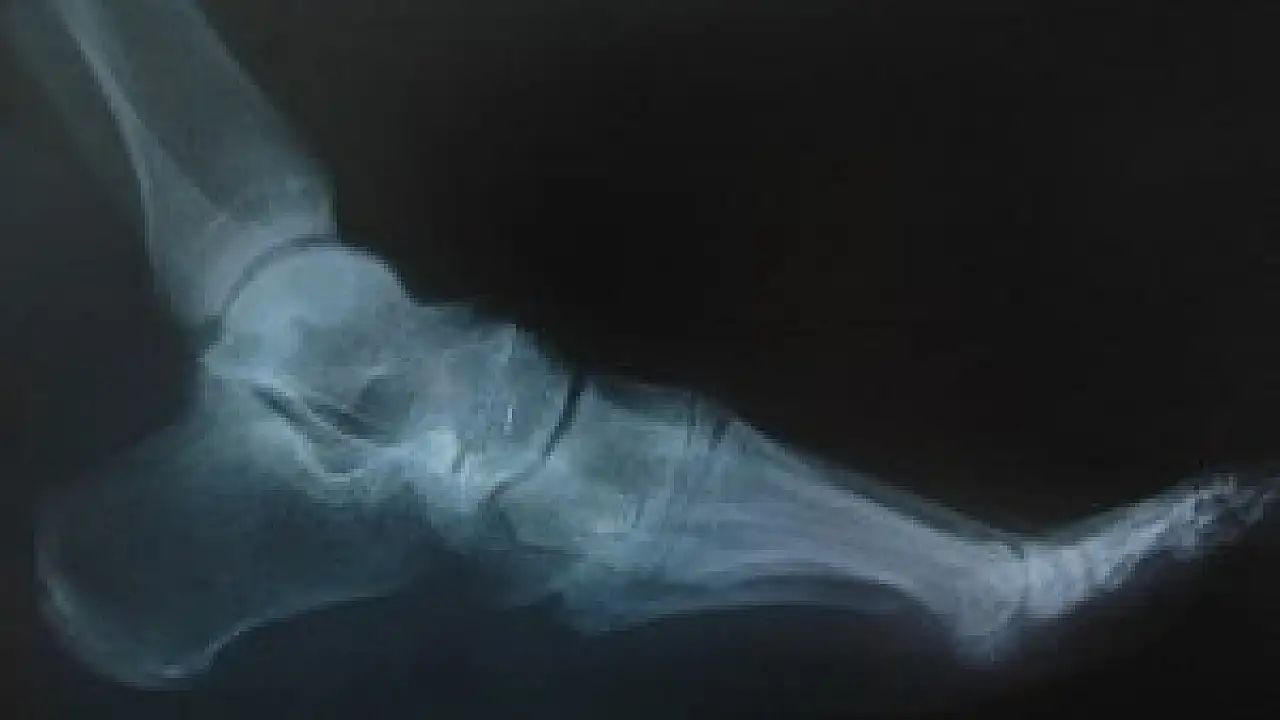

Sonuçları Nature Communications dergisinde yayımlanan araştırmada, yüzde 100 ipekten yapılmış vidaların, fareler üzerinde kırıkların tedavisi için kullanıldığı belirtildi.

ABD'deki Tufts Üniversitesi'nde görevli bilim adamları, özel kalıplar yardımıyla tıbbı kullanıma uygun ipekten vidalar yaptı ve bu vidalar, farelerin bacaklarının arkasında kırılan noktalara yerleştirildi. İpekten vidalar, kemikleri başarılı bir şekilde bir arada tuttu ve araştırmanın sonunda da çözünmeye başladı.

İpek, sertliğinin kemiğe benzemesi ve vücutta eriyerek yok olması özelliği dolayısıyla geleneksel metal plakalar ve vidalarla karşılaştırıldığında ümit verici bir biyomühendislik malzemesi olarak kabul ediliyor.